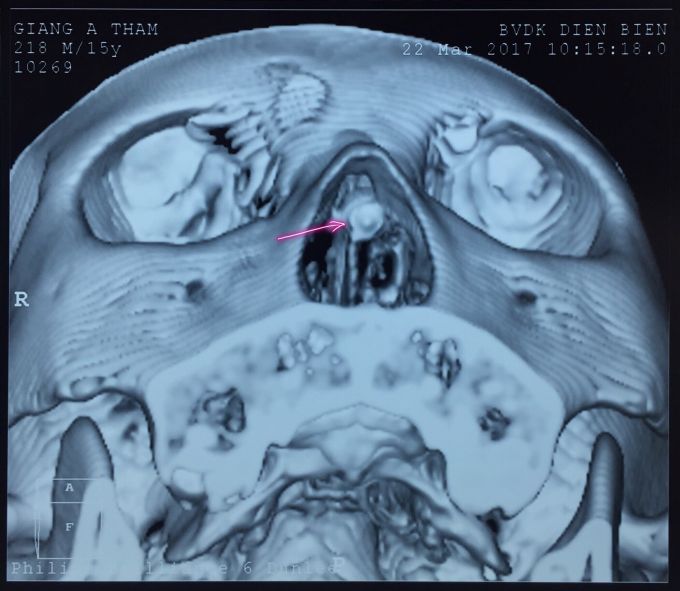

Vị trí của viên đạn.

Bác sỹ Đinh Ngọc Tuấn cho hay, nhận thấy đây là một trường hợp tổn thương nặng, đường đi của viên đạn phức tạp (qua rãnh lợi môi, xuyên qua vách ngăn mũi từ bên phải sang bên trái và dừng lại ở xoang sàng trái), lại nằm ngay gần sọ não. Do đó, việc lấy viên đạn rất khó khăn và nếu không cẩn trọng có thể gây các biến chứng nguy hiểm cho các cơ quan xung quanh.